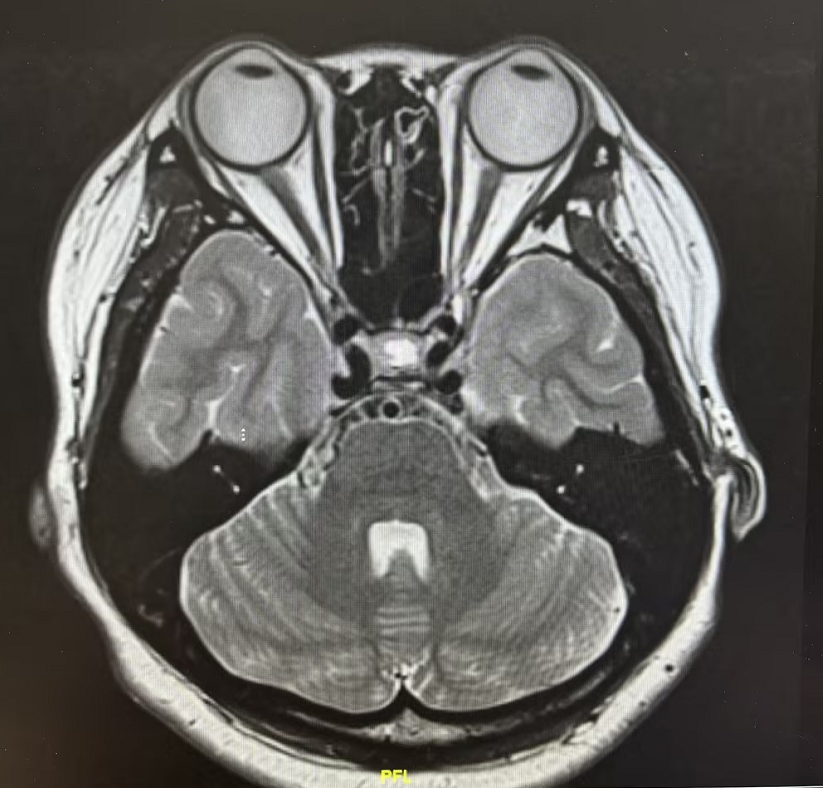

患者为21岁年轻女性,因“月经紊乱6月余”来院就诊。当地医院MRI提示垂体占位,激素检验显示泌乳素高达273ng/ml(较正常值高了11倍)。经我院神经外科进一步评估,确诊为垂体瘤。

术前眼科会诊发现,患者虽自觉视力无明显下降,但视野检查已提示右眼生理盲点扩大、周边颞上方片状视野缺损——这是垂体瘤向上压迫视交叉的早期信号。内分泌科同步介入,全面评估激素水平,为手术保驾护航。术后泌乳素即刻恢复正常,术后6天康复出院。

患者52岁男性,因摔倒致头部外伤急诊入院,行颅脑CT检查意外发现:鞍区占位性病变。入院后进一步检查显示,患者泌乳素升高,性腺、甲状腺、肾上腺皮质功能均减退,考虑为垂体瘤压迫正常垂体组织有关,手术指征明确。